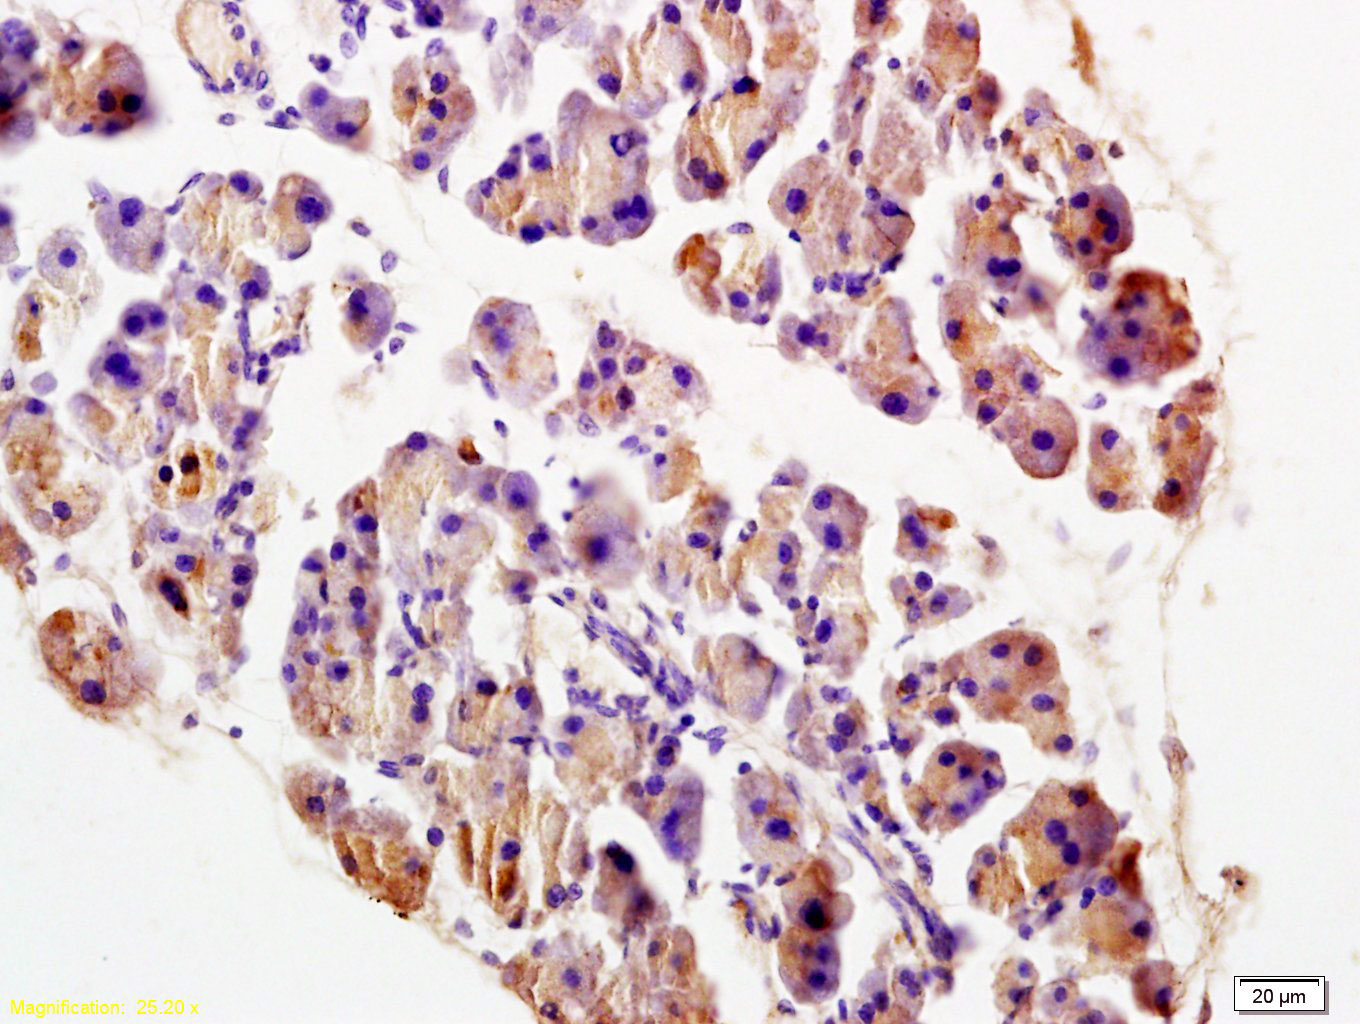

Tissue/cell: rat pancreas tissue; 4% Paraformaldehyde-fixed and paraffin-embedded; Antigen retrieval: citrate buffer ( 0.01M, pH 6.0 ), Boiling bathing for 15min; Block endogenous peroxidase by 3% Hydrogen peroxide for 30min; Blocking buffer (normal goat